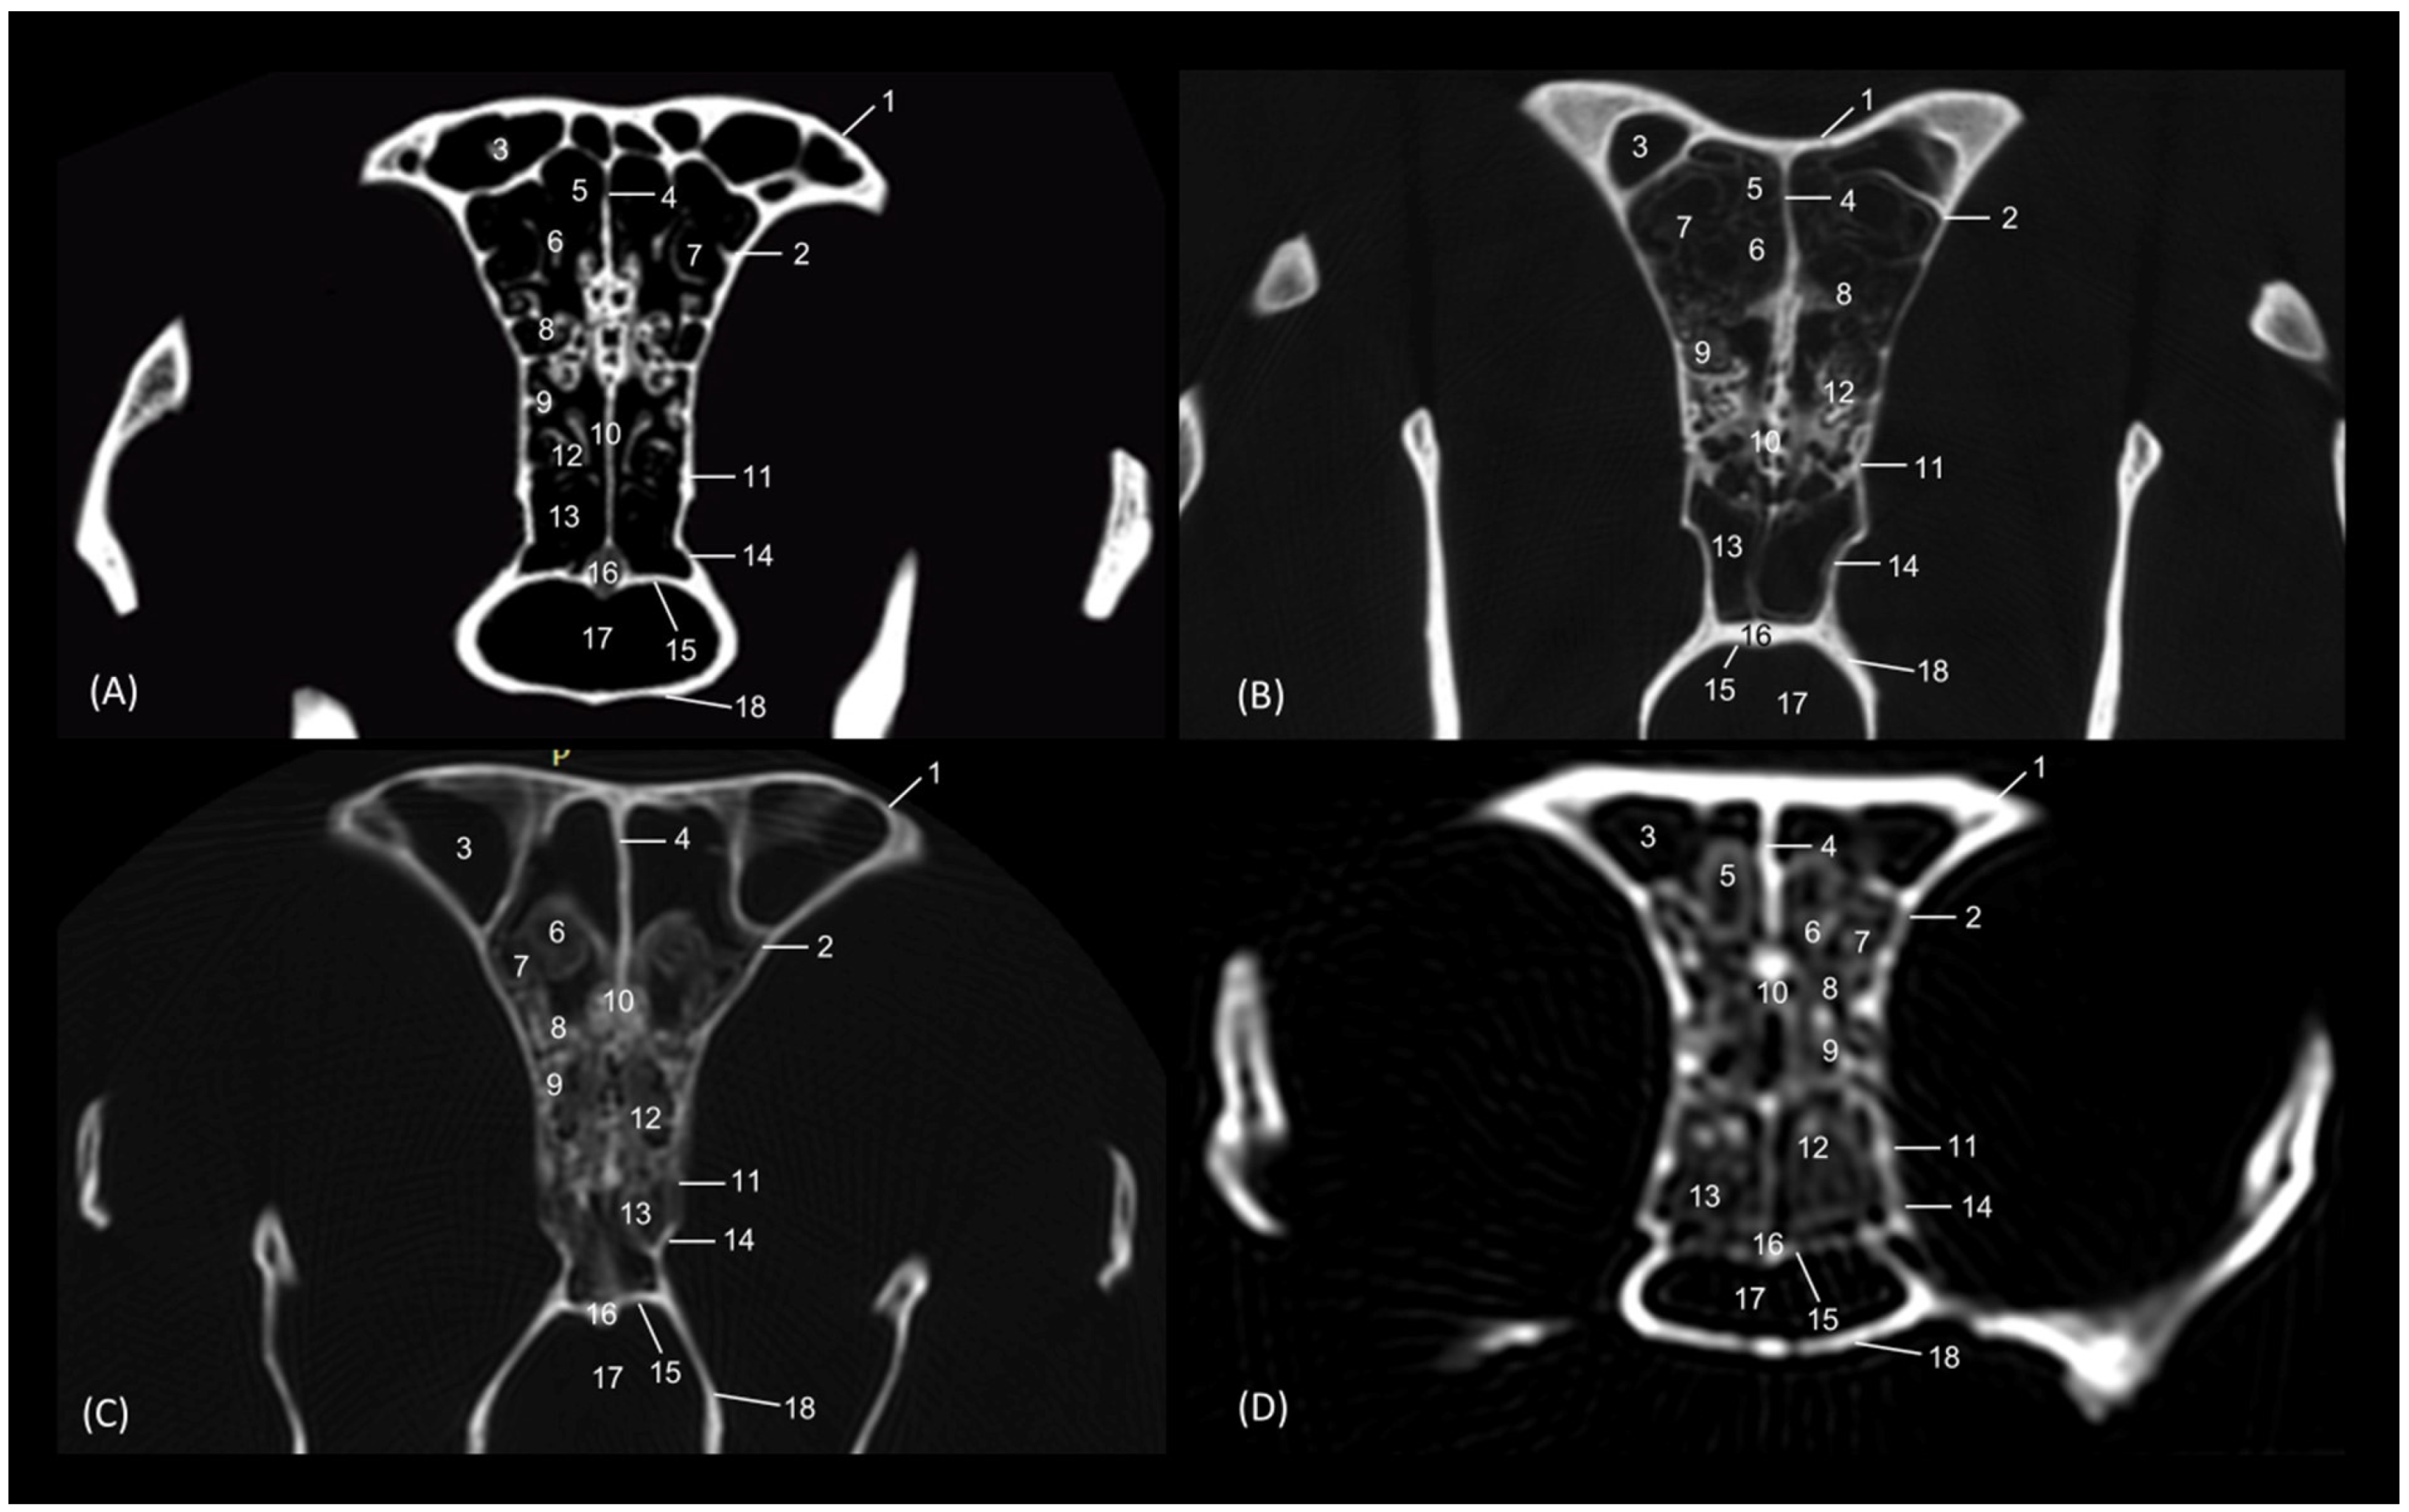

3.4. Felid Skulls CT

The section levels of each plane are represented in Figure 19. The CT study of the felid skull allowed for the identification in the three spatial anatomical planes of the bony base that makes up this cavity: transverse, sagittal and dorsal (Figure 20, Figure 21, Figure 22, Figure 23, Figure 24, Figure 25 and Figure 26). This study has been carried out on the leopard, the lion, the cheetah and the cat.

The nasal bone extends less rostrally in lions than in the other felids. This is seen in Figure 20, where in a rostral cross-section the nasal bone does not cover the roof of the nasal cavity, and again in Figure 25, shown in a sagittal view. Ventrally, the vomer, as well as the palatine process of the maxilla could be clearly observed in the four species in this first level of transverse section (Figure 20). The rostral end of the conchae could not be visualized very well in the leopard or the lion. This fact could also be seen in the sagittal sections (Figure 25B,C). In the cheetah and the cat, the dorsal ventral nasal conchae could be identified as thin, slightly hyperattenuated lamellae. The frontal sinus begins to be observed in the following more caudal sections.

Figure 20. Amira representative transverse CT images at level of the rostral portion of the respiratory part, level I. Images are oriented so that the left side of the head is to the right and the dorsal is at the top. All views are rostral. (A): Leopard; (B): Lion; (C): Cheetah and (D): Cat. 1. Nasal bone; 2. Maxilla; 3. Maxilla: palatine process; 4. Canine tooth: root; 5. Vomer; 6. Dorsal nasal concha; 7. Ventral nasal concha.

In a more caudal cross-section, the frontal sinus is visible in the leopard and the cat (Figure 21A,D), but not in the lion or the cheetah. The development of the middle and ventral nasal conchae could already be seen, as well as the great development of the third endoturbinate. Lateral to the ventral nasal concha, the maxillary recess could be identified. The infraorbital foramen was clearly observed at this level in all four species.

Figure 21. Amira representative transverse CT images at level of the middle portion of the respiratory part, level II. Images are oriented so that the left side of the head is to the right and the dorsal is at the top. All views are rostral. (A): Leopard; (B): Lion; (C): Cheetah and (D): Cat. 1. Nasal bone; 2. Frontal bone; 3. Maxilla; 4. Zygomatic bone; 5. Infraorbital canal; 6. Ethmoid bone: tectorial plate; 7. Maxilla: palatine process; 8. Nasal septum; 9. Vomer; 10. Dorsal nasal concha; 11. Middle nasal concha; 12. Ventral nasal concha; 13. 3rd endoturbinate; 14. Maxillary recess; 15. Frontal sinus; 16. Dorsal nasal meatus; 17. Common nasal meatus; 18. Ventral nasal meatus.

Figure 22 shows the greater thickness of the frontal bone and maxillae of the lion compared to the other species studied. At this level, the temporal process of the zygomatic bone is visible in all four species and the third endoturbinate reaches its greatest development. This was observed as a set of hyperattenuated lamellae on the medial part of the nasal cavity. The ventral nasal concha was already very small in all four species. Ectoturbinates were seen at this level only in the domestic cat. The frontal sinus was now apparent in the cheetah, but not yet in the lion. The tectorial plate of the ethmoid bone was seen as a hyperattenuated area at the base of the frontal sinus.

Figure 22. Amira representative transverse CT images at level of the middle portion of the respiratory part, level III. Images are oriented so that the left side of the head is to the right and the dorsal is at the top. All views are rostral. (A): Leopard; (B): Lion; (C): Cheetah and (D): Cat. 1. Frontal bone; 2. Maxilla; 3. Zygomatic process: body; 4. Zygomatic bone: temporal process; 5. Infraorbital canal; 6. Ethmoid bone: tectorial plate; 7. Maxilla: palatine process; 8. Nasal septum; 9. Vomer; 10. Dorsal nasal concha; 11. Middle nasal concha; 12. 3rd endoturbinate; 13. Ventral nasal concha; 14. Maxillary recess; 15. Frontal sinus; 16. 1st ectoturbinate; 17. 2nd ectoturbinate; 18. 3rd ectoturbinate; 19. Dorsal nasal meatus; 20. Common nasal meatus; 21. Ventral nasal meatus.

Animals 14 02609 g022

In the caudal section of the respiratory part of the nasal cavity (Figure 23), the frontal sinus could be observed in the four species. In it, the three ectoturbinates could also be identified as areas limited by hyperattenuated lines, the first and second being more medial and the third developing lateral to these. At this level, the ventral nasal concha could no longer be visualized. We observed that the body of the presphenoid bone closes the caudal wall of the nasal cavity. The space between it and the horizontal and perpendicular plates of the palatine bone forms the choana or the nasopharyngeal opening. The bony borders of the choanae could be seen in the leopard, while in the other species it was no longer ossified.

Figure 23. Amira representative transverse CT images at the level of the caudal portion of the respiratory part, level IV. Images are oriented so that the left side of the head is to the right and the dorsal is at the top. All views are rostral. (A): Leopard; (B): Lion; (C): Cheetah and (D): Cat. 1. Frontal bone: external plate; 2. Frontal bone: orbital surface; 3. Frontal sinus; 4. Frontal sinus: septum; 5. 1st ectoturbinate; 6. 2nd ectoturbinate; 7. 3rd ectoturbinate; 8. Dorsal nasal concha; 9. Middle nasal concha; 10; Ethmoid bone: perpendicular plate; 11. 3rd endoturbinate; 12. 4th endoturbinate; 13. Presphenoid bone: wing (orbital surface); 14. Presphenoid bone: body; 15. Vomer; 16. Choana; 17. Palatine bone: horizontal and perpendicular plates.

The last transverse section shows the olfactory part of the nasal cavity (Figure 24). In this section, the ethmoid bone was hyperattenuated, specifically the perpendicular plate, the caudal continuation of the nasal septum. The fourth endoturbinate could now be visualized as a thin hyperattenuated line at this level close to the floor of the nasal cavity.

Figure 24. Amira representative transverse CT images at the level of the olfactory part of the nasal cavity, level V. Images are oriented so that the left side of the head is to de right and the dorsal is at the top. All views are rostral. (A): Leopard; (B): Lion; (C): Cheetah and (D): Cat. 1. Frontal bone: external plate; 2. Frontal bone: orbital surface; 3. Frontal sinus; 4. Frontal sinus: septum; 5. 1st ectoturbinate; 6. 2nd ectoturbinate; 7. 3rd ectoturbinate; 8. Dorsal nasal concha; 9. Middle nasal concha; 10. Ethmoid bone: perpendicular plate; 11. Basisphenoid bone: wing (orbital surface); 12. 3rd endoturbinate; 13. 4th endoturbinate; 14. Presphenoid bone: wing; 15. Presphenoid bone: body; 16. Vomer; 17. Choana; 18. Palatine bone: horizontal and perpendicular plates.